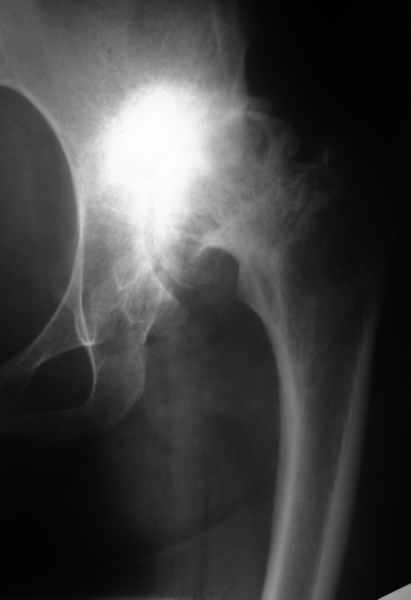

Пациентка 32 лет с диспластическим левосторонним коксартрозом 3 ст. Из анамнеза - в детстве операции по поводу врожденного вывиха левого бедра (остеотомия таза по Хиари и остеотомия проксимального отдела бедра, аппаратное удлинение голени) В настоящее время беспокоят боли в левом тазобедренном суставе, ограничения движения (сгибание 60 гр, отведение 20 гр, общ ротация 30 гр); укорочение левой н/конечности на 5 см. Пациентка ставит задачу о полноценности тазобедренного сустава и коррекции длины нижней конечности. Р-гр прилагаются.

Какой тип эндопротеза оптимален в данном случае? Как проводить коррекцию укорочения? (аппаратное удлинение голени после протезирования?)